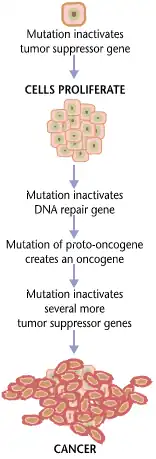

O processo de formação do câncer, denominado carcinogênese ou oncogênese, ocorre lentamente através do acúmulo de mutações, que ao longo do tempo podem resultar na formação de células cancerígenas que proliferam-se dando origem a tumores. O desenvolvimento inicial do câncer ocorre em três estágios, o de iniciação, promoção e progressão do câncer, que estão intrinsecamente relacionados com processos evolutivos como a mutação e a seleção.[28]

A iniciação e a progressão de tumores são considerados processos evolutivos somáticos, impulsionados pelo acúmulo de mutações genéticas, entre as quais podem conferir vantagens de aptidão seletiva à célula hospedeira. [28] Durante a fase de iniciação as células normais sofrem alterações que podem ser provenientes de diversos fatores intrínsecos como mutações genéticas herdadas ou erros aleatórios na replicação do DNA, quanto extrínsecos, por exemplo, a exposição a agentes carcinógenos como radiação, substâncias químicas ou infecções virais, que podem induzir danos e instabilidades genéticas. O desenvolvimento de tumores primários ocorre a partir do acúmulo gradual de mutações ao longo da vida, que podem ser pontuais e neutras ou mutações condutoras de vantagens[28], sendo necessário uma série de modificações genéticas que irão progressivamente agir em genes relacionados aos mecanismos responsáveis por proliferação, diferenciação e morte celular[29]. As mutações resultam em mudanças permanentes no DNA, atingindo principalmente os proto-oncogenes, genes que se mutados podem resultar em crescimento e divisão celular descontrolados, e em genes supressores de tumor, que inibem o crescimento celular descontrolado e promove a reparação do DNA e apoptose.[30]

Durante o estágio de promoção, as células geneticamente alteradas podem sofrer a ação dos oncogenes, ativados pelo acúmulo de mutações, que favorecem a transformação de células normais em cancerígenas, através do crescimento descontrolado de células mutadas.[31] No estágio de progressão tumoral o acúmulo de mutações é intensificado e as células mutadas, agora consideradas pré-cancerígenas, que apresentam vantagens adaptativas em relação às células normais, são selecionadas aumentando o número de subclones com características intensificadas. A seleção das células cancerígenas ocorre no interior dos tecidos do corpo, que evolutivamente adquiriram mecanismos para prevenir o crescimento descontrolado de células anormais, como as cancerígenas, e garantir o funcionamento eficiente do organismo através de propriedades fenotípicas, que se desreguladas podem induzir ou sustentar a malignidade das células cancerosas, levando ao desenvolvimento do câncer.[32] As propriedades fenotípicas podem ser adquiridas através de alterações mutacionais e epigenéticas, sendo as principais a auto-renovação celular, que consiste na capacidade das células se dividirem e renovarem indefinidamente, ocorrendo através da inibição dos genes supressores de tumor e ativação de proto-oncogenes que vão permitir o crescimento descontrolado e a sobrevivência das células anormais; e a estabilização dos telómeros que evita o envelhecimento celular e o encurtamento dos telômeros permitindo que a célula continue a replicar-se[33], que permitem a proliferação, a angiogênese, e a migração celular e evitam a morte celular programada.[30]

O câncer é fundamentalmente uma doença causada pela falha da regulação do crescimento de tecidos. Para que uma célula normal se transforme em uma célula cancerígena, os genes que regulam o crescimento e a diferenciação celular têm de ser alterados.[91]

Os genes afetados são divididos em duas grandes categorias. Oncogenes são os genes que promovem a reprodução e o crescimento celular. Genes supressores de tumores são genes que inibem a divisão celular. A transformação maligna pode ocorrer através da formação de novos oncogenes, da sobre-expressão inadequada de oncogenes normais, ou pela sub-expressão ou desativação de genes supressores de tumores. Normalmente, alterações em vários genes são necessárias para transformar uma célula normal em uma célula cancerosa.[92]